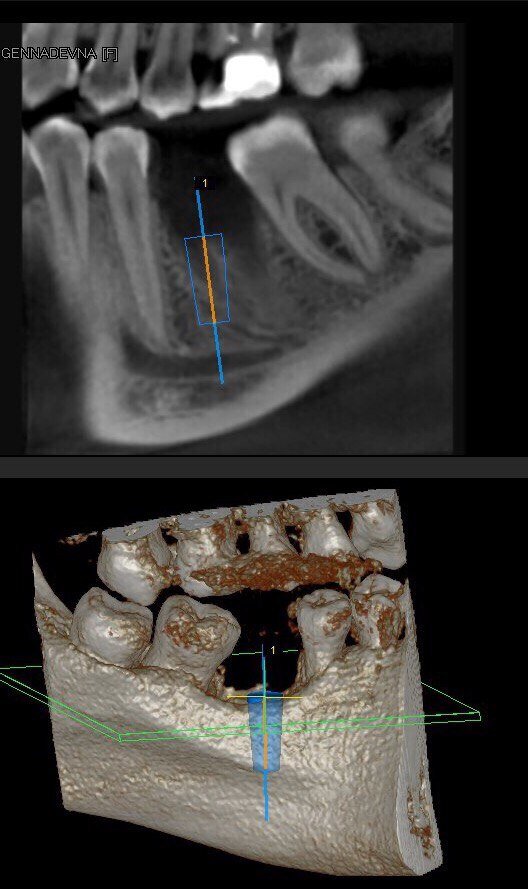

Это имплантация, которая делается отсроченно после удаления зуба. Спустя некоторое время после удаления зуба (от 1 месяца до n-го количества лет). Для планирования операции нужен кт снимок (чтобы индивидуально подобрать размер устанавливаемого импланта), ортопед (кто будет устанавливать коронку) и хирург имплантолог (кто занимается установкой имплантатов). Очень важно сделать кт снимок, потому что только по кт снимку мы можем увидеть ширину, высоту костной ткани и важнейшие анатомические образования, которые мы не должны повреждать фрезой. На 2d изображении этого увидеть нельзя. ! Без кт снимка имплантацию проводить нельзя. Но стоит отметить, что раньше стоматологи производили планирование по оптг (2d) снимку. Говорить о какой-либо точности здесь не приходится. Современная стоматология планирования по 2d снимку не приемлет. Вот стандартные этапы при классической имплантации и количество приёмов:

Очень важно сделать кт снимок, потому что только по кт снимку мы можем увидеть ширину, высоту костной ткани и

важнейшие анатомические образования, которые мы не должны повреждать фрезой. На 2d изображении этого увидеть нельзя.

• Рентген контроль направления фрезы и будущего расположения импланта в костной ткани.

-10

Рентген контроль установленного имплантата.